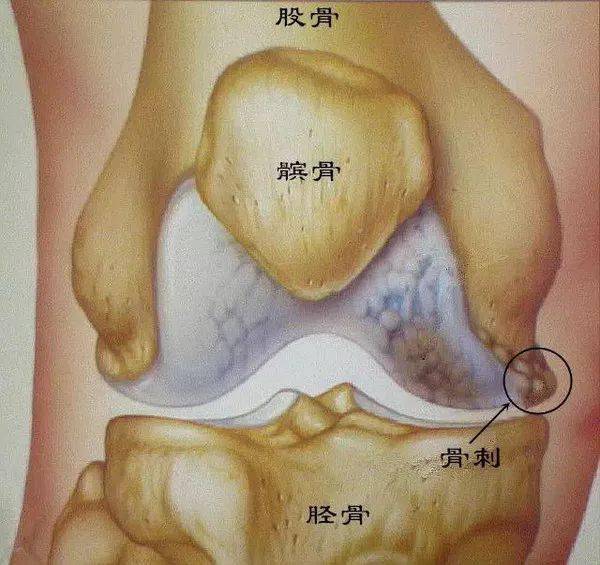

什么是骨刺?

骨刺也被称为骨质增生、骨赘,是正常的骨头多长出来一部分,有相当一部分人会有骨质增生,其中又以膝关节最为常见。

随着年龄的增长,骨关节也会逐渐退化,当骨头与软组织接触的地方因长期承受压力、拉力、损伤,造成关节间的软骨渐渐失去水分与弹性,骨头与骨头磨损,人体为了减小骨、关节之间的压力,在骨关节边缘上自然而然就会增生一部分来减少这个压力。

它本质上是人体生理上的代偿功能,是人体为适应力的变化而产生的一种自我保护反应。

因为关节软骨受到破坏,长了“骨刺”后,它可以使稳定性差的骨关节得以加强,从而有利于骨关节的稳定性,避免继续遭到损伤。

骨刺也可能造成对其周围神经、血管等的压迫,出现相应的临床症状;所以说它既是生理性的,但又可能转变为病理性的。我们要一分为二地看,不能把临床上表现出来的症状全部都归罪于骨刺。